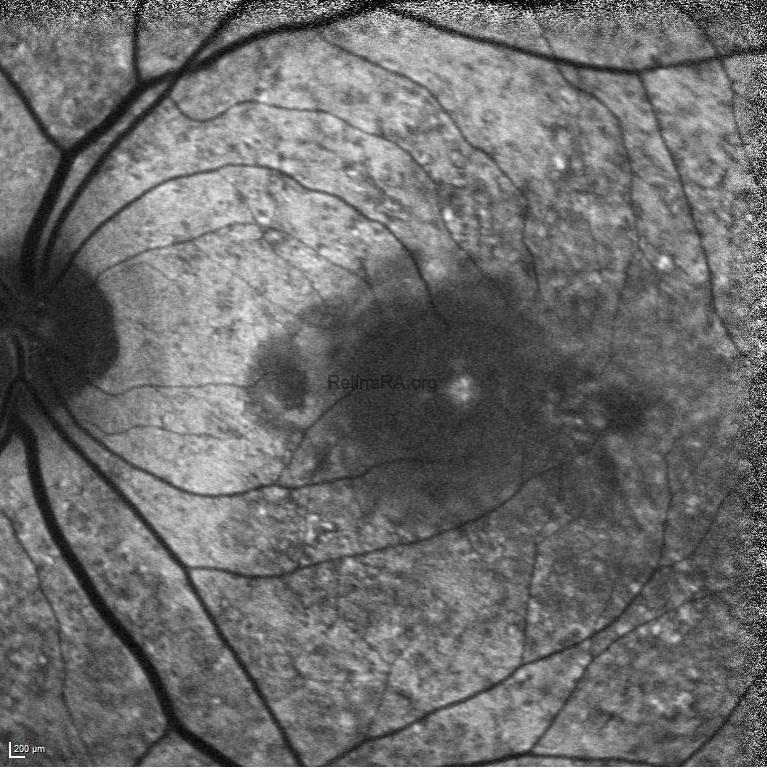

On ocular examination, the BCVA was 20/20 in the right eye and 20/400 in the left eye. IOPs were within normal limits in both eyes and anterior segment examinations were unremarkable. Dilated fundus examination of the right eye revealed a normal optic disk with a classical rubella retinopathy findings — a classic salt-and-pepper appearance of the retina that is due to the distribution of areas of increased and decreased pigmentation. In the left eye, in addition to classical rubella retinopathy findings appearance, a whitish subretinal lesion with retinal hemorrhages in the macula was detected. Mottling of the RPE was also evident in both eyes.

Fundus fluorescein angiography illustrated a pattern of diffuse spotty fluorescence because of the defective RPE without any leakage or staining in the right eye. On the left eye, in addition to diffuse spotty fluorescence, an active subfoveal CNV lesion, that hyperfluoresces in the early phases of the FFA, maintains well-demarcated borders, and leaks, was detected.

Fundus autofluorescence highlighted the fundus abnormalities patchy auto-fluorescence with a stippled hypo-fluorescence in both eyes, and also an hypo-autoflorescence area corresponding to the area of choroidal neovascularization in the left eye.